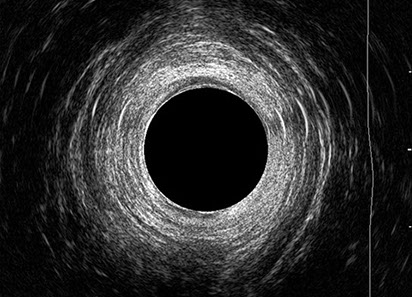

L’ecografia transanale è un esame diagnostico per immagini che consiste nell’introduzione di un trasduttore ad ultrasuoni. Le immagini qualitativamente migliori del canale anale sono ottenute usando un trasduttore rotante, montato in un manipolo rigido, che fornisce un’immagine a 360°. Con le apparecchiature più moderne è anche possibile ottenere immagini tridimensionali.

L’ecografia transanale permette di distinguere la sottomucosa che riveste il canale anale, lo sfintere anale interno, e lo sfintere anale esterno.